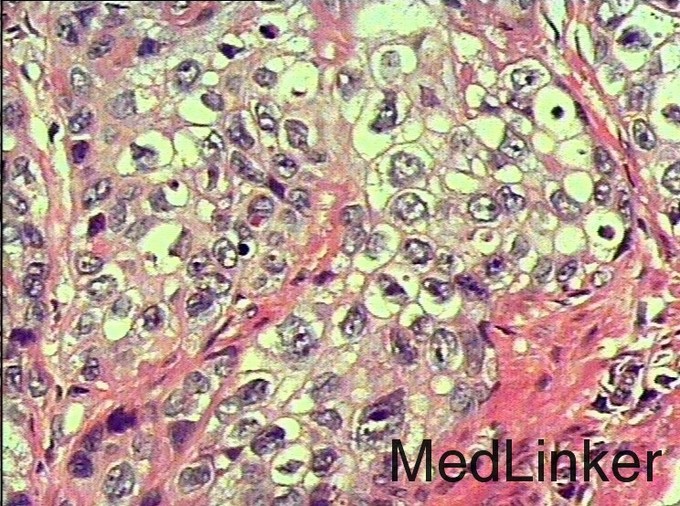

诊断:输尿管癌? 治疗:经术前准备,行右侧输尿管镜镜检+肿物活检术,手术顺利,术后病理示:高级别浸润性尿路上皮癌。与家属充分沟通及完善术前准备后,行腹腔镜下右肾、右输尿管癌根治性切除术,手术顺利,术后恢复较好,术后病理示:符合高级别浸润性尿路上皮癌。

讨论:输尿管恶性肿瘤多来源于输尿管上皮组织,以移行细胞癌最常见,移行细胞癌多呈乳头状生长,突入腔内,约1/3为多发性肿瘤。影像表现为输尿管、肾盂和肾盏不同程度扩张积水,并于输尿管梗阻端发现软组织肿块或腔内有充盈缺损,增强扫描轻中度强化,集合临床表现,多可作出诊断,不过应注意输尿管癌的多发性,勿漏诊!